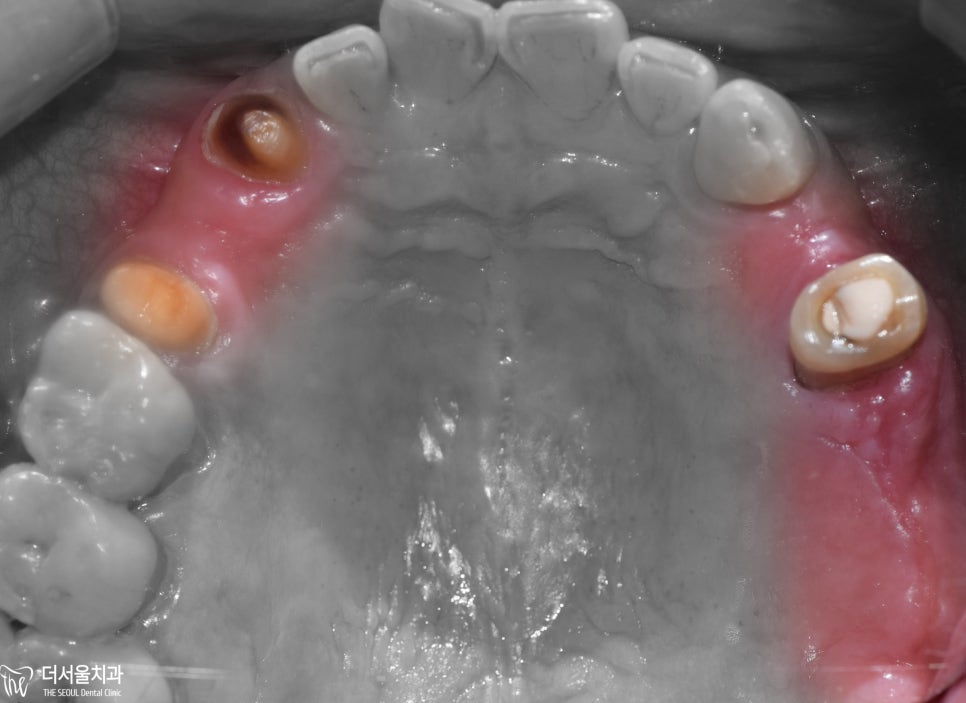

먼저

위턱부터 살펴보면

왼쪽/오른쪽 할 것 없이 치아를 상실했는데

더군다나

치료를 받다가 중단했는지

보철을 씌우지 않은 채로 방치된 모습을 보였습니다.

아래턱을 살펴보면

오른쪽 부위를 상실하였으며

골폭이 줄어든 것을 확인할 수 있었습니다.

오랫동안 치료받지 않고

방치한 만큼

구강 상태가 좋지 못했습니다.